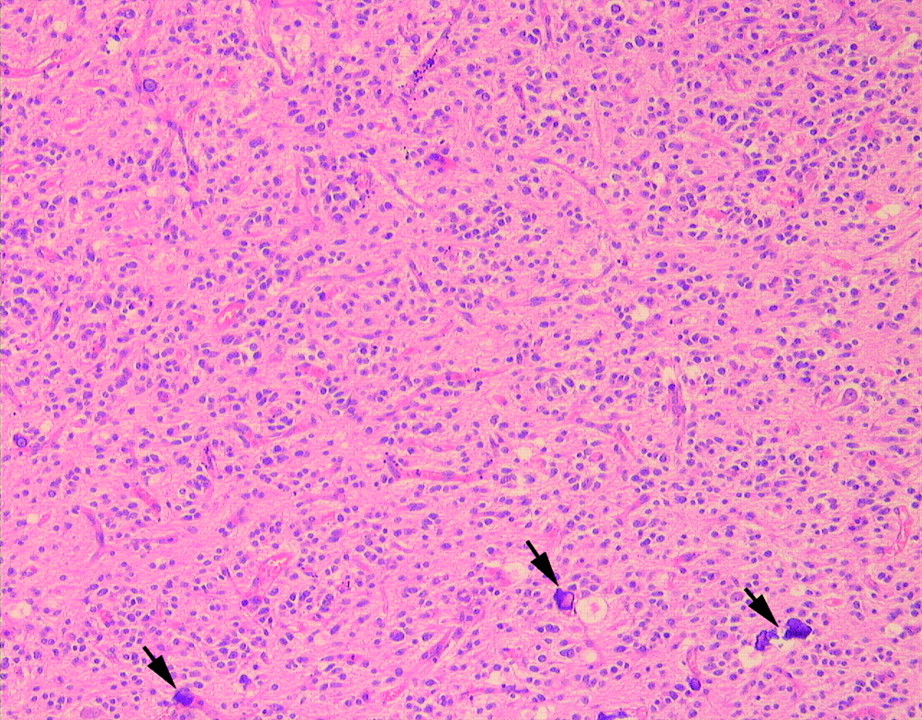

Микрофотографии гистологии глиобластомы головного мозга